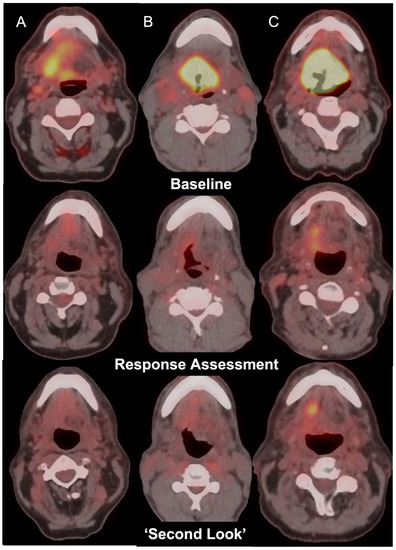

Clinical Utility of Second-Look FDG PET-CT to Stratify Incomplete Metabolic Response Post (Chemo) Radiotherapy in Oropharyngeal Squamous Cell Carcinoma

| Second-Look PET Activity | ||

|---|---|---|

| Active Primary on Initial Response Assessment PET-CT | Active Lymph Node on Initial Response Assessment PET-CT | |

| Progression | 20 | 10 |

| Stable | 20 | 14 |

| Complete response | 20 | 13 |